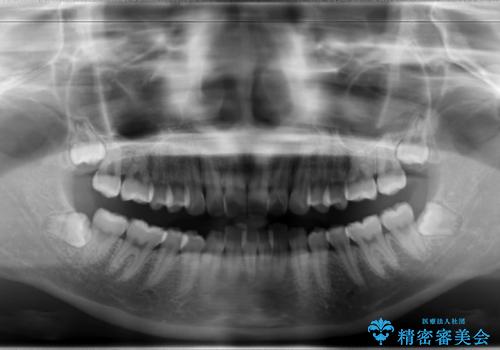

Invisalign インビザラインによる軽度なガタつきの改善

- 奥歯の位置関係はそこまで大きくいじらず、前歯群のみでガタつきの改善を計画しました

奥歯の位置関係に改善の余地はありますが、機能的に問題のない cusp to fossa の関係で咬めているため、前歯のガタつきを前歯のみで改善するというシンプルな計画で、短期間で治療を終了させました。